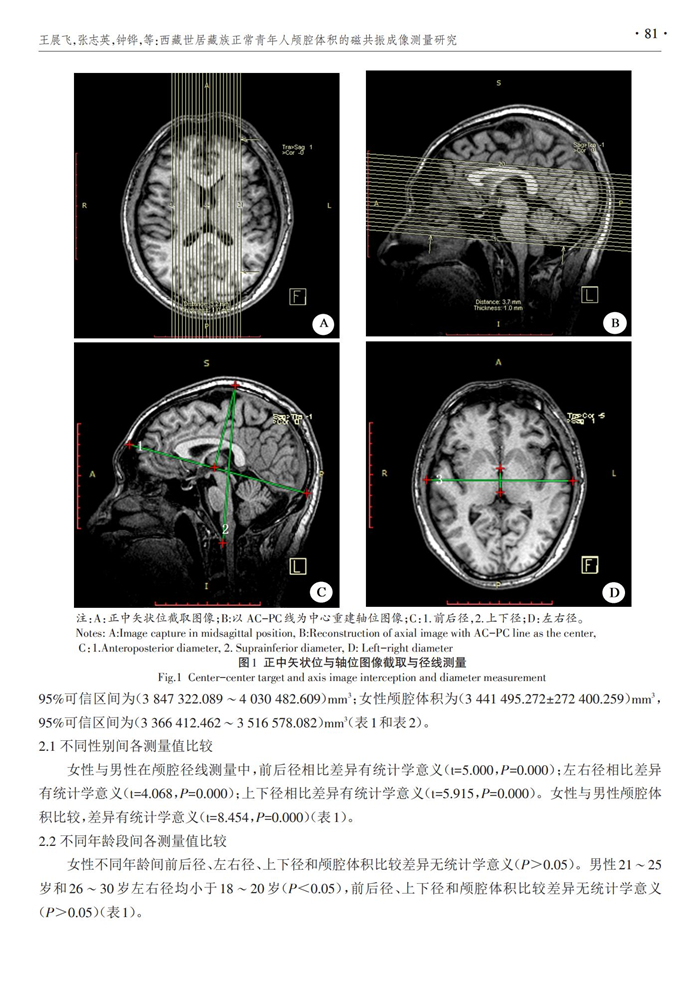

西藏世居藏族正常青年人顱腔體積的磁共振成像測量研究